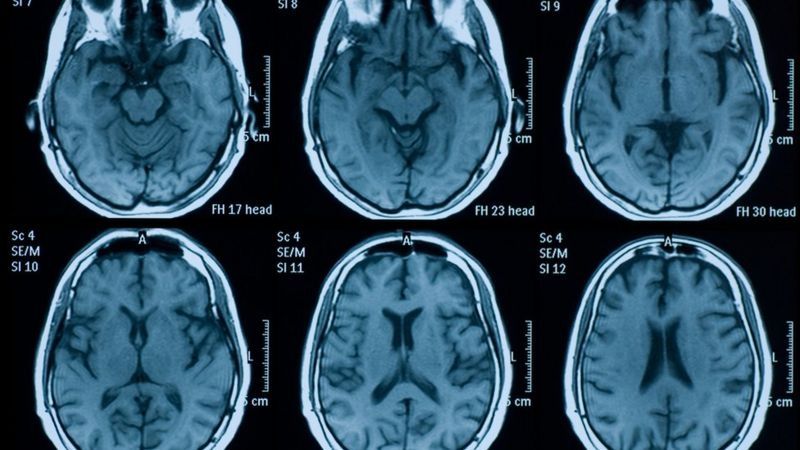

La neuropsicóloga Barbara Sahakian, de la Universidad de Cambridge en Reino Unido, ha estado analizando los efectos del distanciamiento social y la ansiedad por la pandemia en nuestra masa cerebral.

"A través de escáneres a personas socialmente aisladas hemos detectado cambios en el volumen de las regiones temporales, frontales, occipitales y subcorticales, así también como en el hipocampo y la amígdala", le dice Sahakian a BBC Mundo.

En 2018, por ejemplo, un estudio publicado en la revista Neurology de la Academia Estadounidense de Neurología demostró que un alto nivel de cortisol en pacientes se asoció con una peor memoria y percepción visual, así como con volúmenes más bajos de materia gris total, occipital y lobar frontal.

Sahakian y su equipo han estado investigando las variaciones en nuestro cerebro que provoca la pandemia.